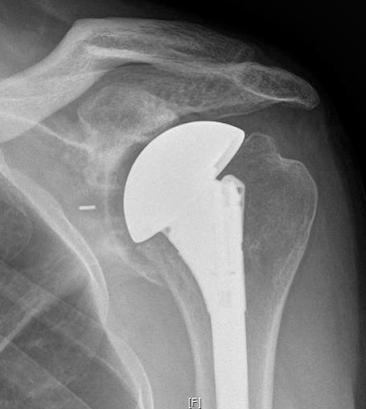

We just met for the first time a 40 year old male laborer who at the age of 30 had a hemicap apparently for shoulder arthritis. While we do not have his preoperative films, his post op is shown here.